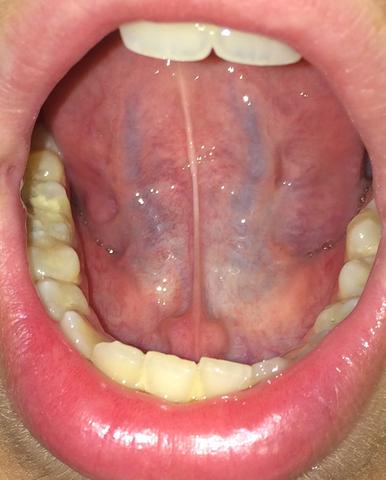

Ranula Wikipedia